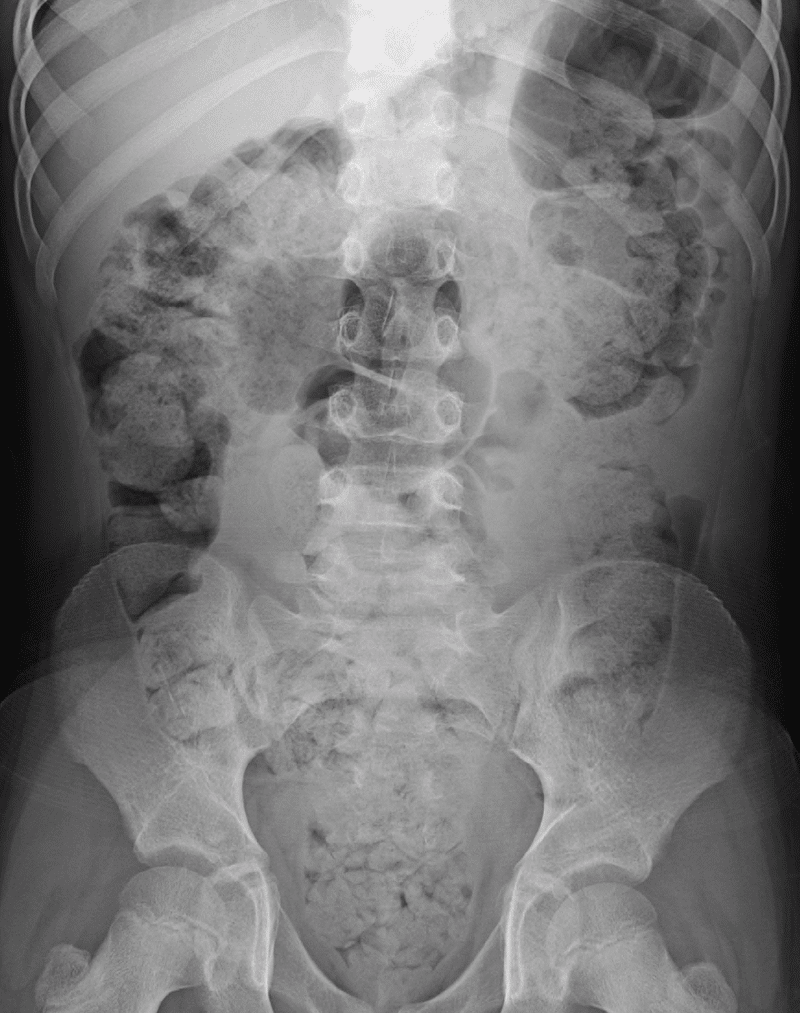

Severe Constipation on X-ray

Significant constipation in the plain X-ray of an 8-year-old. Notice the large amounts of fecal matter (white) surrounded by gas (black) in the large intestine